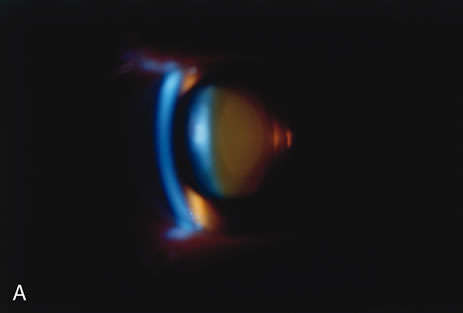

to each other (Figs. 2, 5, 6, and 7).   Fig. 2. Brunescent (brown) nuclear cataract using (A) narrow beam slit illumination and (B) retroillumination. The cataract is best seen by direct slit illumination. In

retroillumination, as seen in this image, the outline of

the nuclear cataract may be seen due to its increased refractive index, although

the cataract does not cast any shadows. Because of its central

location, this cataract may cause distortion of images early in their

development. Fig. 2. Brunescent (brown) nuclear cataract using (A) narrow beam slit illumination and (B) retroillumination. The cataract is best seen by direct slit illumination. In

retroillumination, as seen in this image, the outline of

the nuclear cataract may be seen due to its increased refractive index, although

the cataract does not cast any shadows. Because of its central

location, this cataract may cause distortion of images early in their

development.